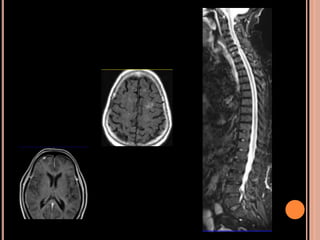

44 year old male, known case of left temporal low grade Glioma

operated upon 6 years back with post-operative RT has now

presented with suspected recurrence.

Simultaneous PET MRI provided information regarding FDG uptake, rCBV, rCBF, Choline/Creatine

and Choline/ NAA ratio from each tissue element at the same time, making a diagnosis of

recurrence accurately that subsequently proved on histology following resurgery.

44 year oldmale, known case of left temporal low grade Glioma operated upon 6 years back with post-operative RT has now presented with suspected recurrence. Simultaneous PET MRI provided information regarding FDG uptake, rCBV, rCBF, Choline/Creatine and Choline/ NAA ratio from each tissue element at the same time, making a diagnosis of recurrence accurately that subsequently proved on histology following resurgery.